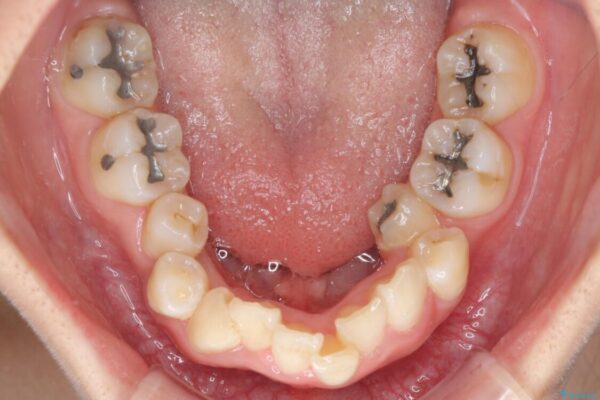

内側に倒れ込んだ歯や下の前歯が隠れてしまうほどの咬み合わせを改善したいとのことで来院された患者様です。

下顎の叢生を解消するために抜歯が必要であり、奥歯の咬み合わせや口元の印象から、上顎も同様に抜歯と判断し、上下左右の第1小臼歯4本抜歯してワイヤー装置にて矯正治療を行うこととしました。

治療前

• デコボコと深い咬み合わせ ワイヤー装置での抜歯矯正 治療前画像